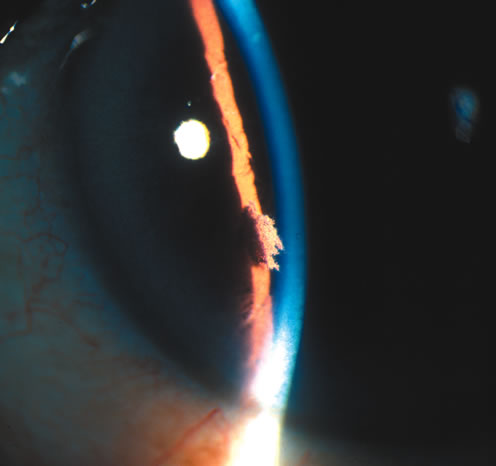

IRIDOSCHISIS Clinical Features Iridoschisis is a rare condition that involves the iris stroma. The term iridoschisis is used when there is a split causing a cleft to occur in the iris stroma. The iris pigment epithelium and dilator muscle posteriorly are unremarkable. Histopathology including transmission electron microscopy shows marked atrophy of the iris stroma with separation of its anterior and posterior layer. The iris vasculature appears unremarkable.6,7 Iridoschisis mainly occurs in elderly8–10 but isolated cases have been reported in young patients after concussive injury.11 It has also been reported to occur as a familial condition,12 has been associated with microphthalmos,13,14 interstitial keratitis,14,15 use of miotics,8 keratoconus,16 and lens subluxation.17 Slit-lamp examination reveals iris stromal fibers and blood vessels that remain attached to one portion of the iris with the loose ends floating freely in the anterior chamber, producing the so-called shredded-wheat appearance. The location of iridoschisis is often inferior (Fig. 3).